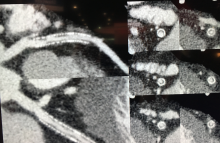

A linear accelerator combined with high-field MRI could soon be on the U.S. market. If U.S. regulators do as expected, it will be the second such system.